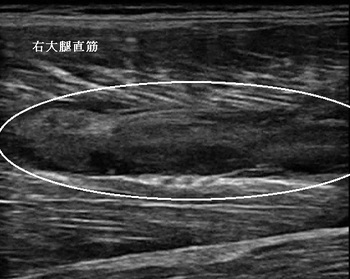

鶴ヶ島市 中学生 もも(大腿部)の痛み 打撲

右大腿上部 超音波画像

鶴ヶ島市 中学生 バスケットボール部所属。 右もも(大腿部)の痛み、打撲(筋挫傷)。

【原因】

バスケ練習試合中、相手の膝が右ももにぶつかりました(所謂、ももカン)。試合後、急速に痛みと腫れが

強く出たため歩くことも困難になりました。

【施術】

その日に来院されましたが、右膝と股関節を曲げることができませんでした。超音波検査では右大腿直筋が

強打され、筋肉の組織が断裂し、内出血していることが認められました。

暫くアイシングして、もものサポーターで固定しました。翌日は痛みが軽減したので内出血の吸収を促進させる

治療器で施術しました。1か月後の試合に向けて施術を継続中です。

1昔前までは、肉ばなれや酷い打撲の治療はアイシングして安静を保持するのが一般的でしたが、現在では

内出血の吸収を積極的に行います。

当院では患部の状態を超音波観察しながら、施術の効果を客観的に評価して最短の完治を目指しています。

スポーツで負傷したねんざや打撲を短期間で治したい方は、当院までお気軽にお問い合わせ下さいね。